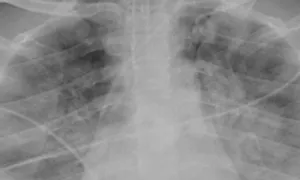

Ngày 10/10, Ths.BS Phó Thiên Phước, Khoa Hồi sức tim mạch, cho biết bệnh nhân tổn thương phổi lan tỏa hai bên, diện tích gần 70% thể tích hai phổi, giảm oxy máu nặng, biểu hiện hội chứng nguy kịch hô hấp cấp, nguy cơ phải can thiệp ECMO (máy hồi sức tim phổi).

Xquang phổi của bệnh nhân trước (bên trái) và sau khi điều trị (bên phải). Ảnh: Bệnh viện cung cấp